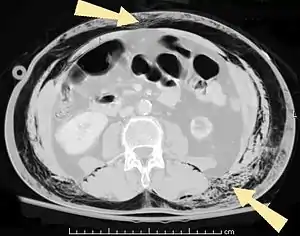

| سیتیاسکن شکم یک بیمار مبتلا به آمفیزم زیر جلدی (ناحیه پیکانها) | |